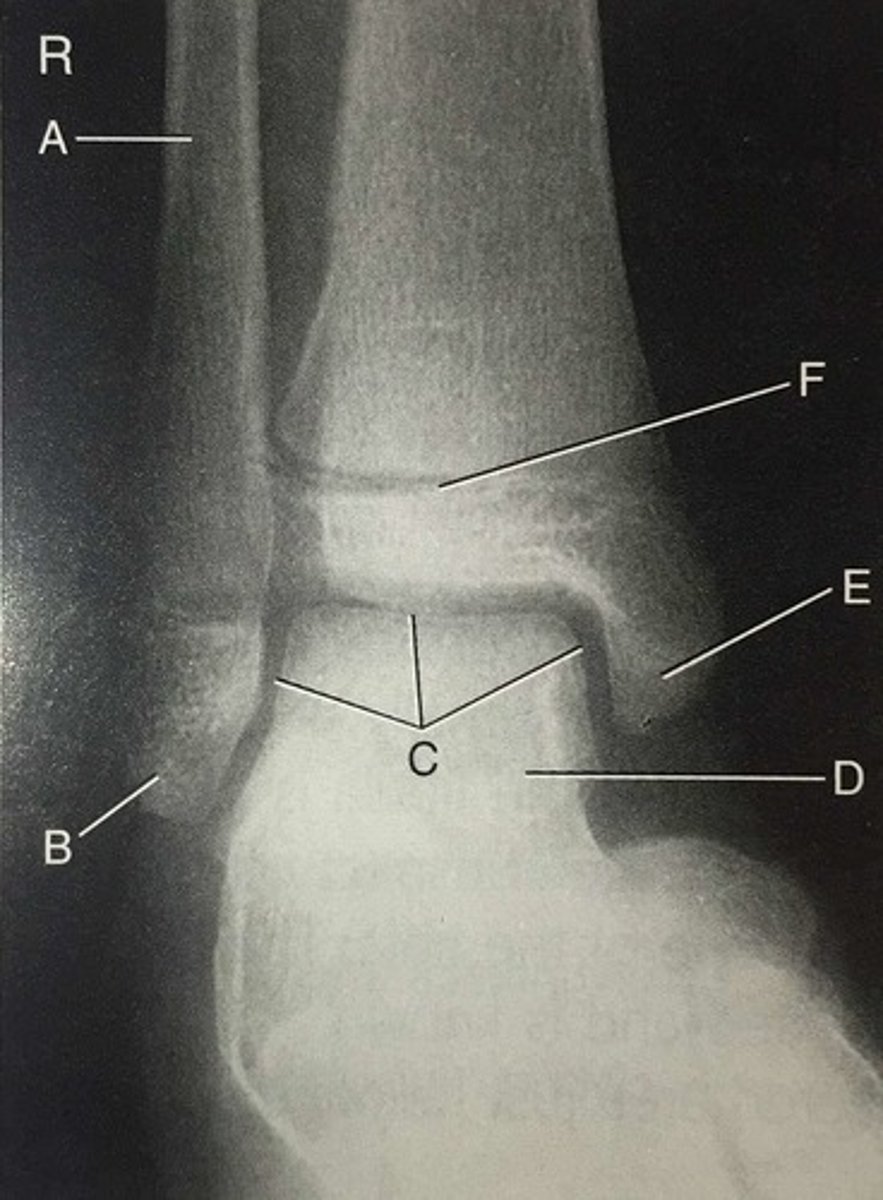

intercondyloid eminence

A

medial condyle

B

proximal extremity

C

anterior crest

D

body of tibia

E

distal extremity

F

medial malleolus

G

anterior tubercle of tibia

tibial plafond

talus

lateral malleolus

5

mortise joint